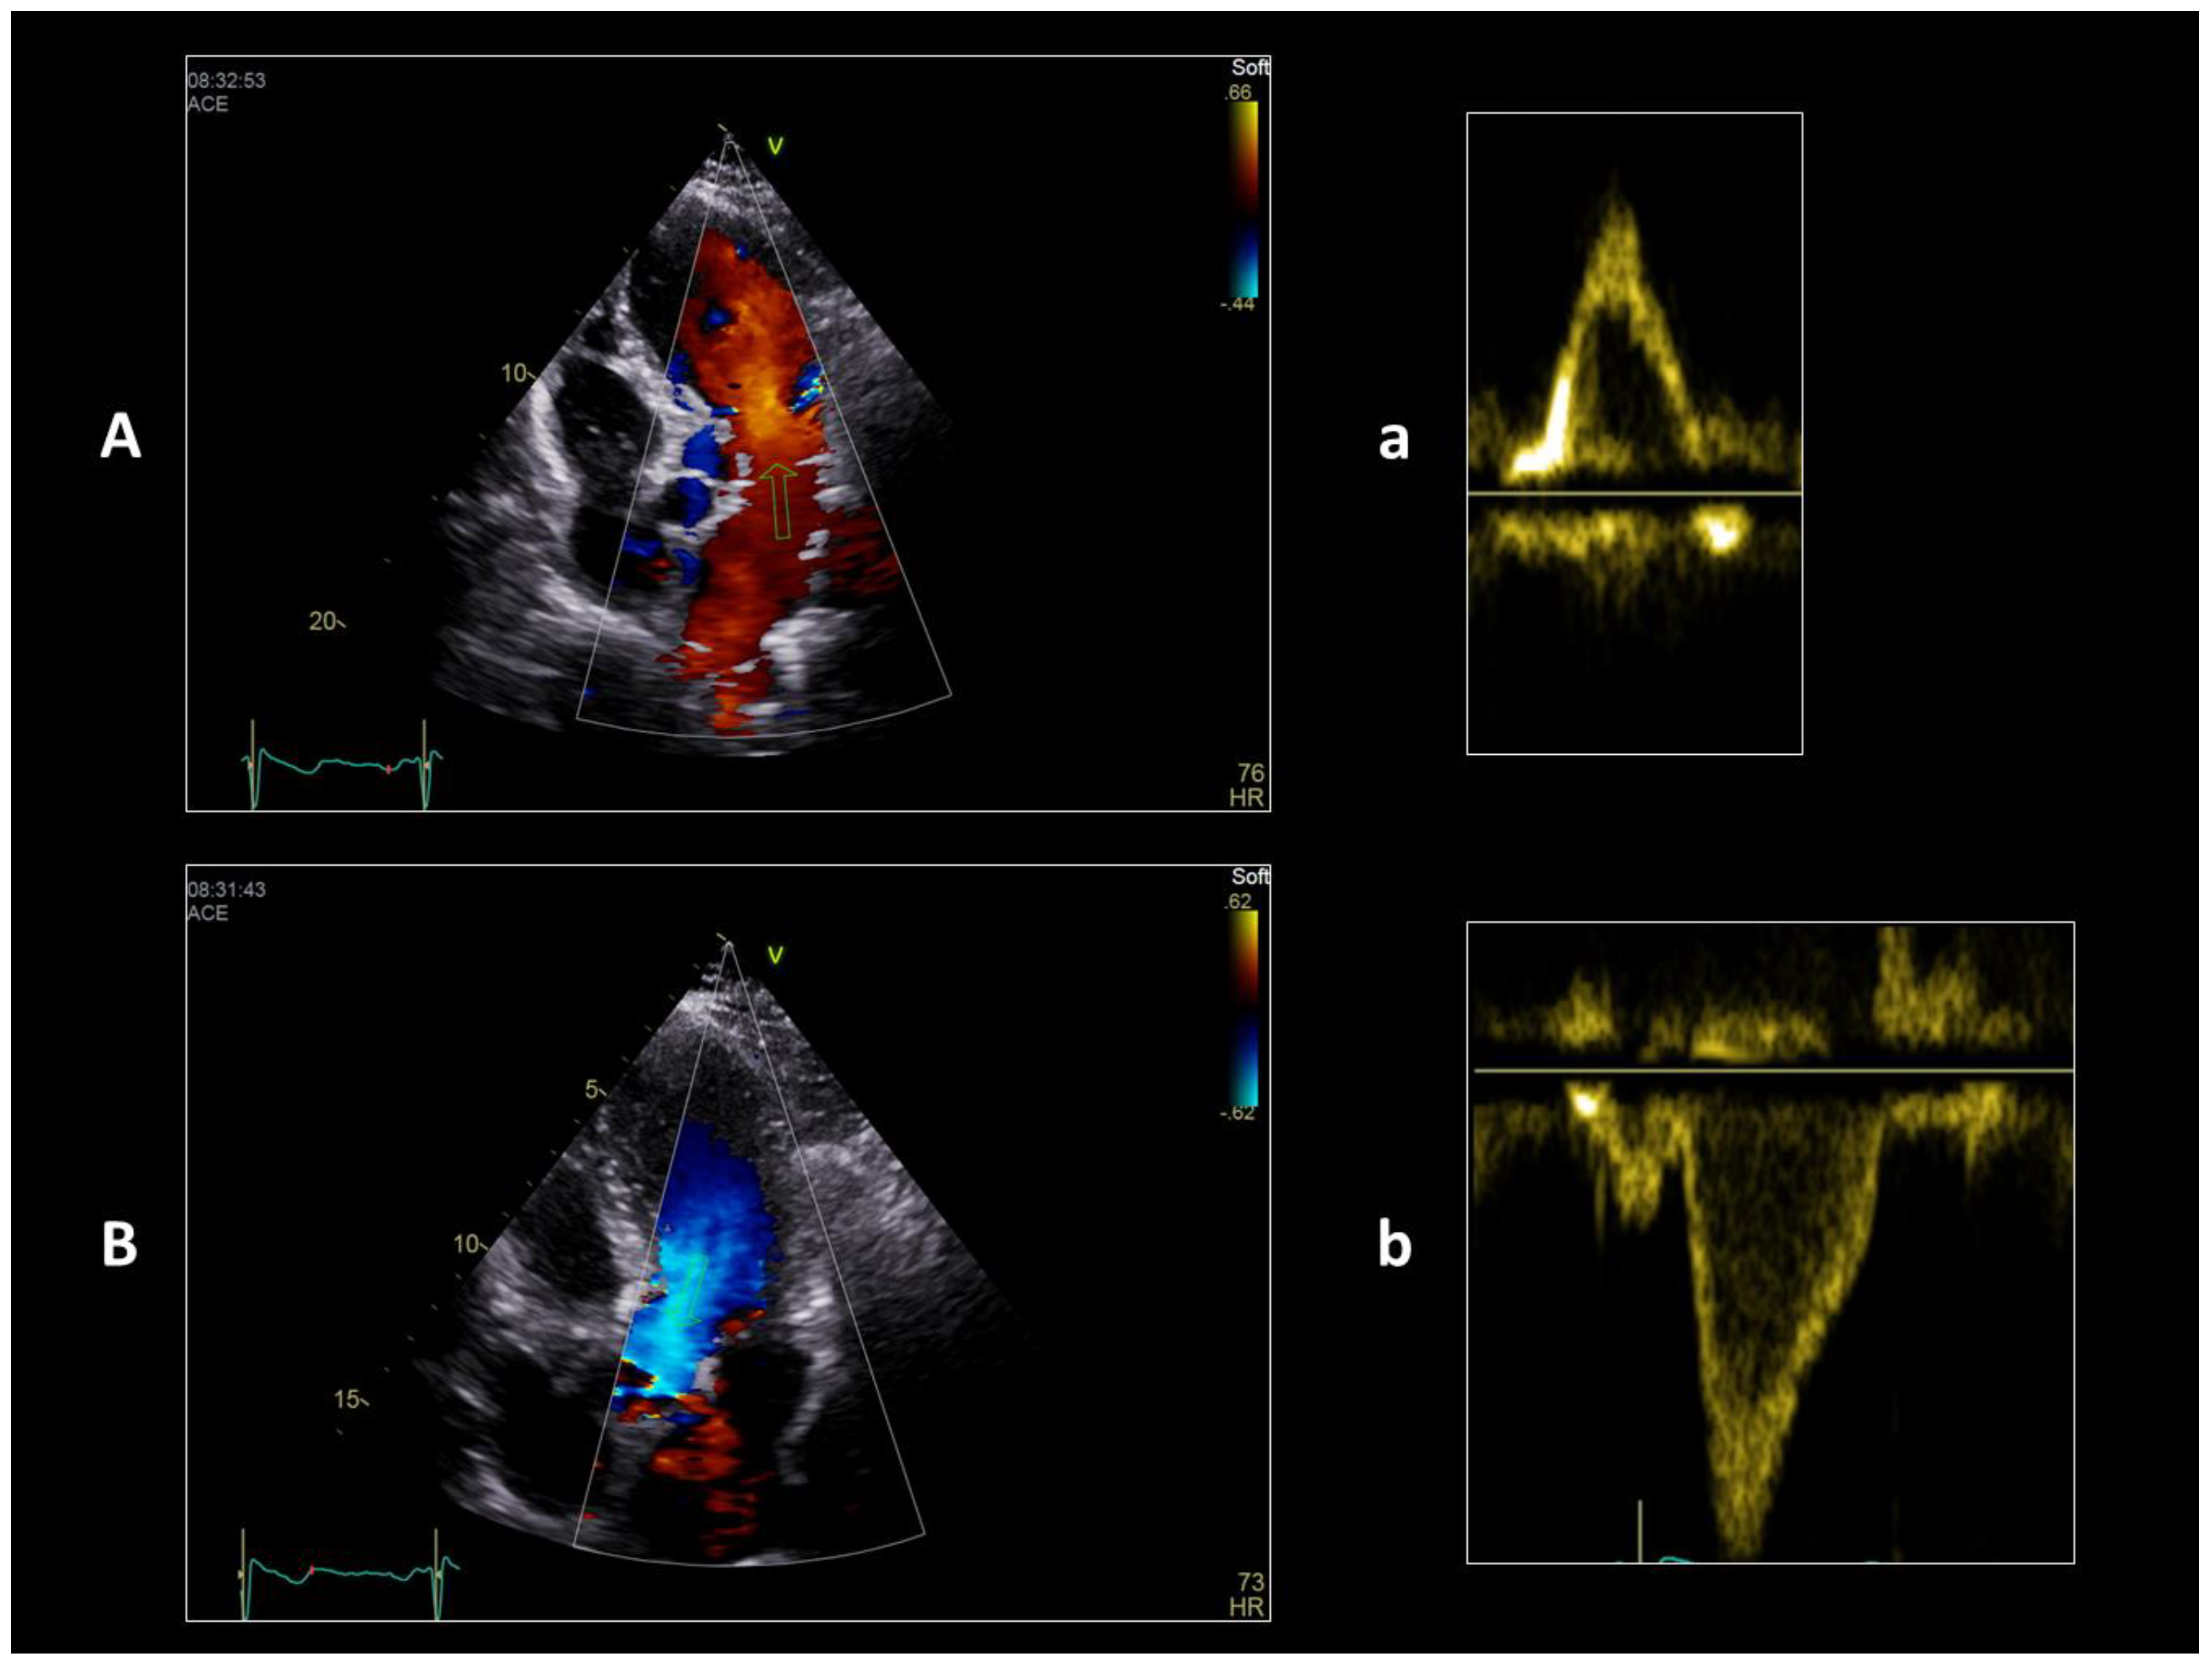

If you imagine bending a straight tube and keeping a linear flow within it, the final shape must have as little bending as possible. The final conical shape of the left ventricle (and also of the right one) recalls a straight tube with a single fold at the apex. The inflow and outflow sections are connected by an acute angle at the apex of the heart. This configuration allows maintaining a laminar flow in both anatomical areas, obtains the almost complete occlusion of the ventricular chamber and exploits the apex as a sort of parabolic curve to favor the blood exit in systole. In this way, also in the elliptical shape of the mature left ventricle, in normal conditions, the blood flow maintains a linear pattern, just following the curved apical region. Although it is an important variation in the linear aspect of the blood path, the elliptical shape of the ventricle with the presence of the cardiac apex has been positively selected exploiting the diastolic vortex, an important parameter in the dynamics of the blood. The profound modifications due to the looping also induce a chiral [47] asymmetry of the flow in the cavities which facilitates the separation of the inflow from the outflow [48]: the left ventricle works in practice according to a first-in first-out mode and in physiological conditions the complete passage of a certain amount of blood ends within about nine beats. The first-in first-out mode is still the mode of expulsion of blood from the linear heart tube. As is visible in echo Doppler study of the flow inside the ventricle (Figure 3, Video S1), it has a double linear direction in the cardiac cycle, down from the mitral valve to the apex in diastole and up from the apex towards the aortic valve in systole.

The two components of the flow are both linear and are connected by the apical vortex during the diastolic phase, which accounts for the transportation of 10% of the whole filling volume. The septation of the ventricular cavity doubles this configuration in a “W” shape of the left and right flows of blood (Figure 4).

The following are available online, Video S1: Echocardiographic flow pattern of the left ventricle in a healthy volunteer, slow motion. The diastolic (red) and systolic (blue) components of the flow are both laminar, with no turbulence (see the homogeneous full color, no mosaicism, only normal aliasing for systolic flow acceleration). Video S2: Surgical view of a normally contracting heart. The torsion motion is evident in the apical region, which is raised up to a better view (slow motion). Video S3: Pre- and post-operative echocardiographic standard and 2D speckle tracking (ST) study in a 73 year-old female patient operated by KISS procedure. Standard echo shows key modifications obtained by the described technique: elliptical shape, small volume, new apex and the reduction in tenting of the mitral valve due to the restoration of a near-normal ventricular chamber. 2D ST echo shows the preoperative abnormal clockwise rotation of the dilated apex with fibers disarranged and the postoperative near-normal counterclockwise rotation of the restored new apex with fibers re-oriented. The two controls differ by a few days.